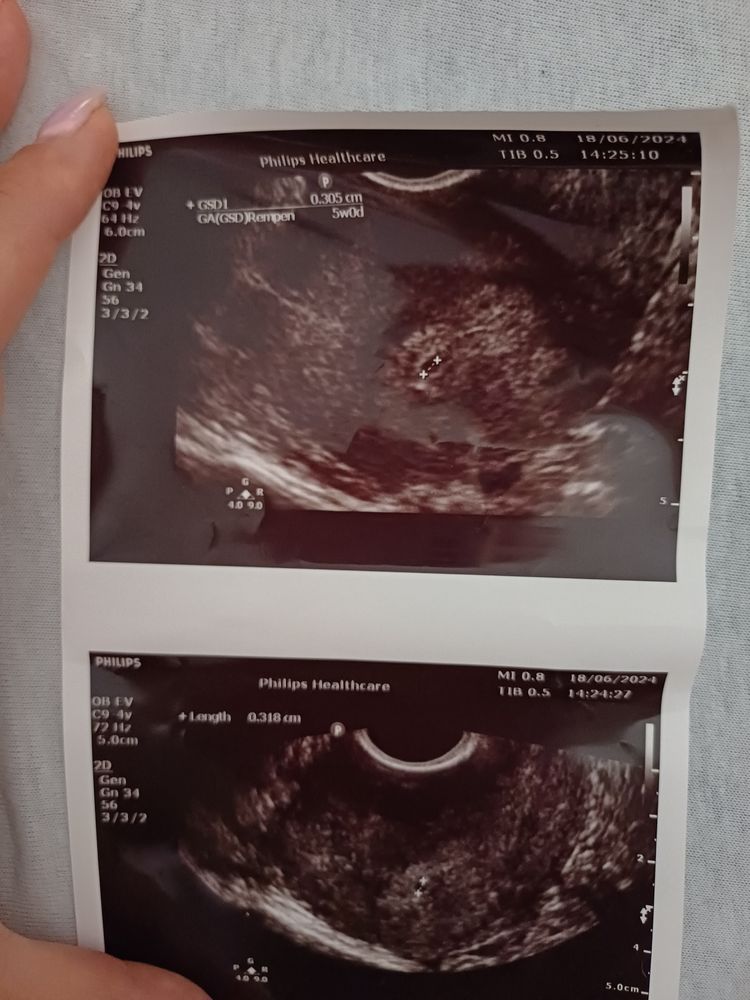

Виктория , На узи сходила сегодня, доктор сказал что точно не может сказать есть ли пя, вернее не уверен что это оно, сказал повторить через 2 дня. Вот такое заключение, получается расстроилась ещё больше

Виктория , Изображение

Виктория , вот посмотрите пожалуйста 🙏

Denizcik , я пока тоже не могу понять, может кто-то из девочек подскажет Что вам точно сейчас нужно, это успокоится в первую очередь и не подсаживаться на панику, пока повода нет и даст бог и не будет, сейчас бусинке нужна спокойная мама в первую очередь, чтобы покрепче закрепится на весь срок 🙏 все будет хорошо, главное верить и не боятся заранее того,чего нет